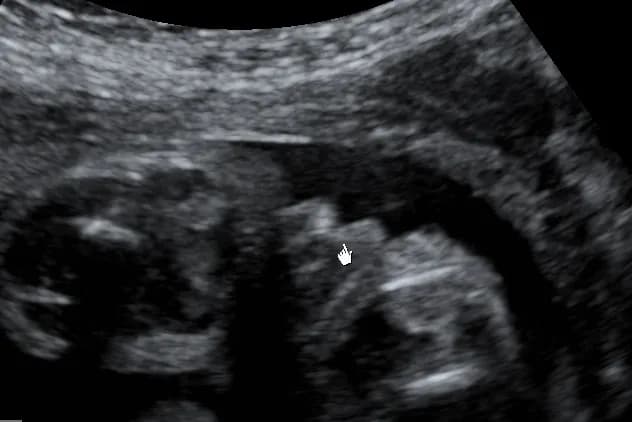

Badanie ultrasonograficzne (USG) w 12. tygodniu ciąży jest jednym z pierwszych momentów, kiedy można próbować określić płeć dziecka. W tym czasie lekarz może zobaczyć rozwijający się płód oraz ocenić jego ogólny stan zdrowia. Jednak rozpoznanie płci w tym okresie jest mało pewne, ponieważ narządy płciowe są jeszcze słabo wykształcone, co zwiększa ryzyko błędnej interpretacji wyników. Dlatego, chociaż możliwe jest dostrzeżenie pewnych cech, lekarze często zalecają poczekać na późniejsze badania.

Warto zaznaczyć, że dokładność tego badania w 12. tygodniu wynosi zazwyczaj około 70-80%. Z tego powodu wiele osób decyduje się na dalsze badania w późniejszych tygodniach ciąży, które oferują wyższą pewność. W przypadku USG połówkowego, które odbywa się między 18. a 22. tygodniem, dokładność wzrasta do około 95%. Warto również pamiętać, że ostateczny wynik zależy od wielu czynników, takich jak jakość sprzętu diagnostycznego oraz układ płodu w macicy.